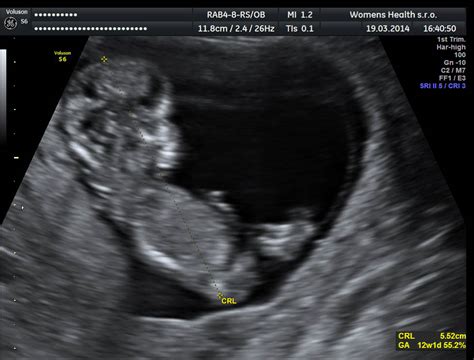

Prvotrimestrálny screening sa vykonáva medzi 10. - 13. týždňom tehotenstva a je dôležitým vyšetrením na včasné odhalenie genetických porúch a vývojových abnormalít plodu. Kombinovaný prvotrimestrálny skríning (odber krvi a ultrazvuk) pomáha odhaliť najčastejšie genetické ochorenia ako Downov, Edwardsov či Patauov syndróm. Pozitívny výsledok ešte neznamená postihnutie. Je však signálom na ďalšie vyšetrenia, ktoré môžu ochorenie potvrdiť alebo vylúčiť.

Počas prvej návštevy u gynekológa sa tehotenstvo oficiálne potvrdí. Pri prvých odberoch sa zisťuje vaša krvná skupina a Rh faktor, vrátane prítomnosti antierytrocytárnych protilátok. Prvý ultrazvuk potvrdí vitalitu bábätka, určí gestačný vek aj početnosť tehotenstva.

- 12. týždeň: PAPP-A screening + ultrazvukový screening + moč (chemicky, sediment, kultivácia).